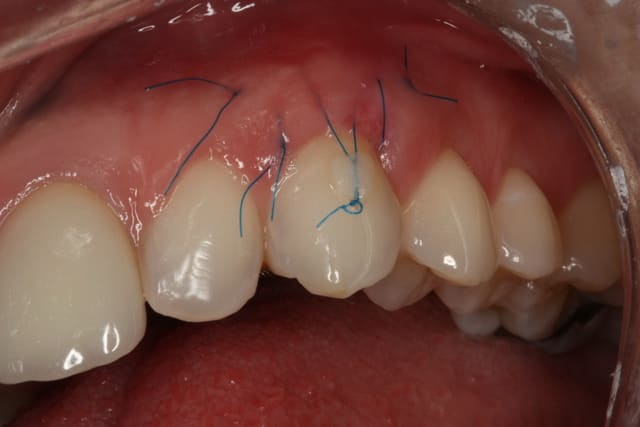

Comme on voit pas bcp de muco sur eugenol

P'tite 23 qui montrait trop de racine

Les 2 dernières photos sont à la dépose des fils (14 jours)

Il y a une "sling suture" pour la traction, le point collé au compo, est en plus, pour tester ;-)

Voici un cas similaire, encore une 23, perte de tissu plus grande, pas de point suspendu avec compo, seulement 2 "sling-suture".

Greffon tracté sous lambeau en mésial et distal comme le cas précédent avec sutures.

Pas d'incision vertical en mésial, surtout que la 22 est un implant, placé trop apical, donc risque de perdre papille distal de 22 +++. Petite incision vertical en distal de 23, pour tracter le lambeau.

Photo final à 4 mois, belle intégration du tissu je pense.